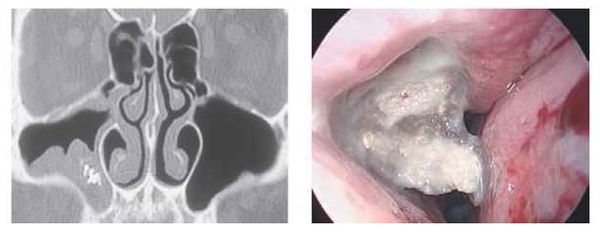

Инструментальная диагностика

Стандартные рентгенологические методы недостаточно информативны, поскольку они не могут дать объёмную послойную картину черепа, как КТ. На рентгенограммах утолщённая воспалённая слизистая оболочка пазухи имеет серый цвет, участки кальцификатов, которые образуют грибы мицетомы, — белый, а воздух — чёрный. Эти участки характерны только для мицетомы.

Мультиспиральная компьютерная томография остаётся эффективным и единственным способом диагностики мицетомы околоносовой пазухи. Использование трёхмерной реконструкции даёт представление об объёмном взаиморасположении костей, позволяет оценить состояние верхнечелюстной пазухи и зубочелюстной системы (целостность зубов, степень разрушения, цвет, положение в зубном ряду, подвижность, глубину зубодесневых каналов), а при наличии инородных тел точно показывает их форму, размер и местонахождение.